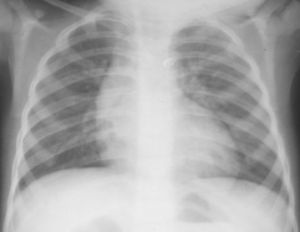

法樂氏四聯症X光片(一)症狀主要是自幼出現進行性紫紺和呼吸困難,哭鬧時更甚,伴有杵狀指(趾)和紅細胞增多。病孩易感乏力,勞累後的呼吸困難與乏力常使病孩採取下蹲位休息,部分病孩由於嚴重的缺氧而引起昏厥發作,甚至有癲癇抽搐。其它併發症尚有心力衰竭、腦血管意外、感染性心內膜炎、肺部感染等。如不治療,體力活動大受限制,且不易成長。